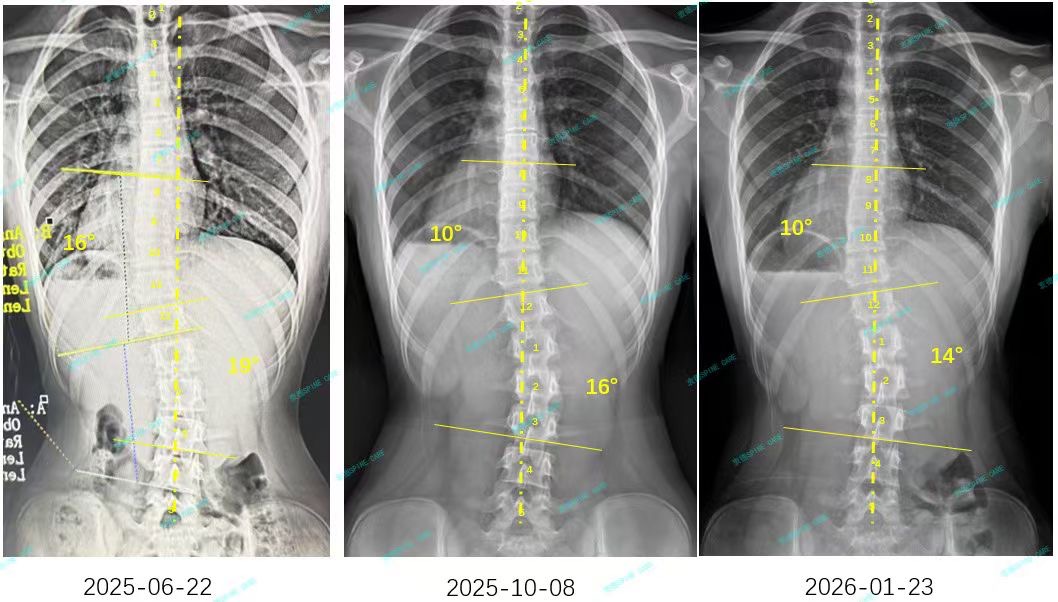

来自家长对衷德的评价(小逸妈妈)

衷德脊柱,我们只关注侧弯保守治疗~